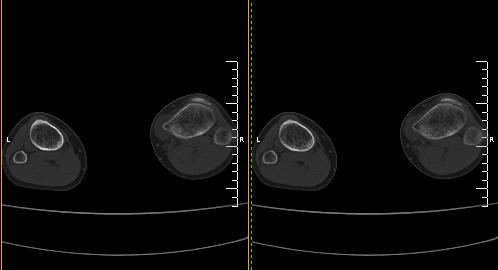

标题: CT19091:右胫骨近段骨性突出. [打印本页]

标题: CT19091:右胫骨近段骨性突出.

男,15岁,右胫骨近段软组织肿胀,下肢疼痛10左右.

右胫骨近端内侧骨性突起,皮质连续,骨质结构正常,首先考虑胫骨骨软骨瘤,随访观察。